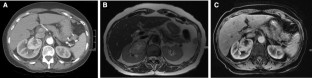

Figure 1